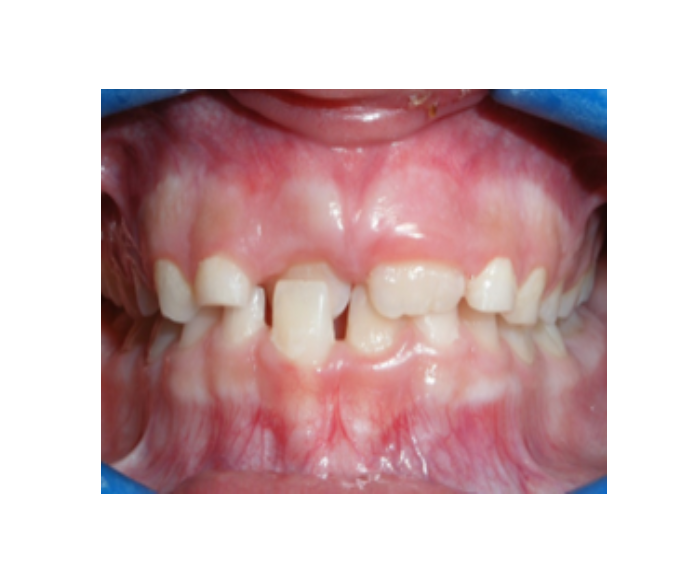

Mordida cruzada posterior bilateral